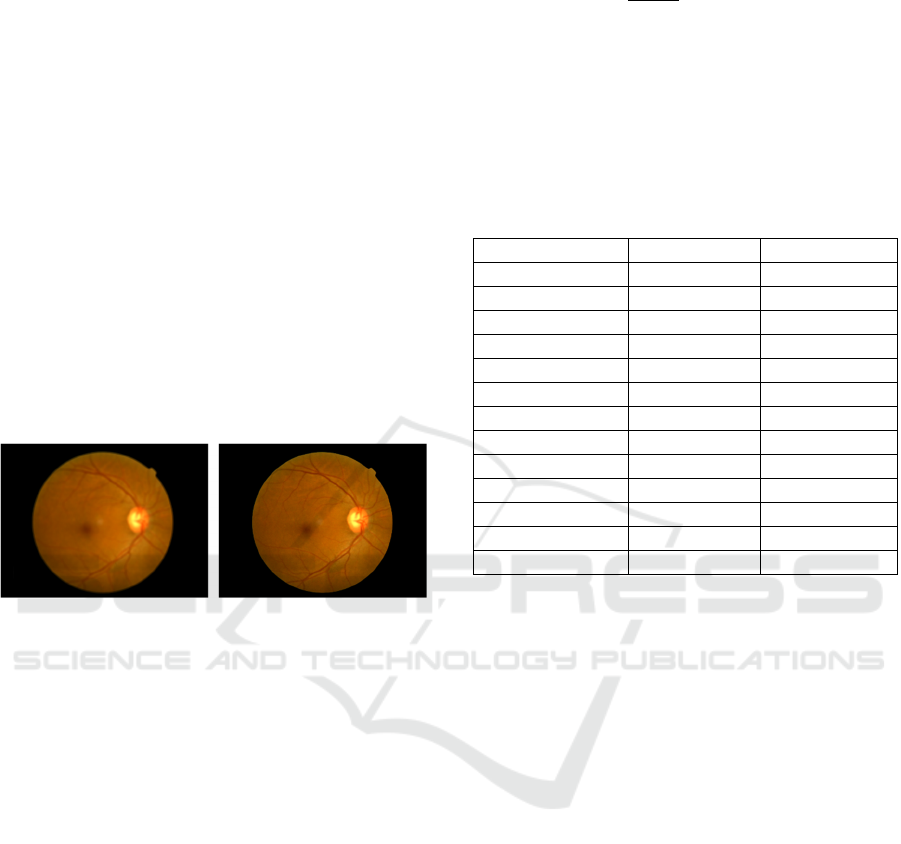

diagnosis. In Figure 1, SRGAN dramatically

increases the quality of fundus images.

Figure 1: Comparison of fundus images before and after

SRGAN processing. (Picture credit: Original)